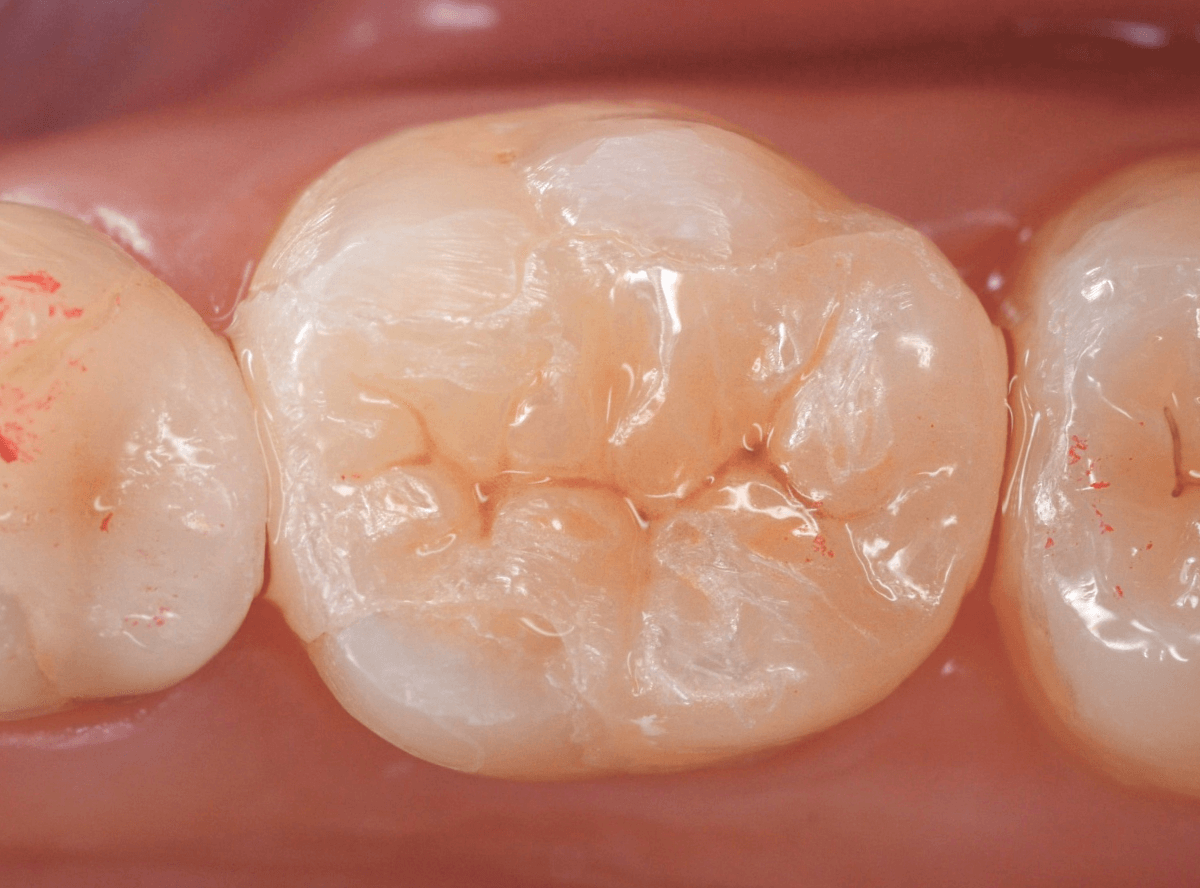

Case.30 上の奥歯のセラミック治療

治療後の状態です。

ジルコニア・インレーはE-MAX・インレーより審美性に劣るのですが、患者さんにもご満足いただける仕上がりになり、ホッとしました。

| 治療回数 | 3回 |

| 治療期間 | 3週間 |

| 費用 | ジルコニア・インレー (70,000円)x2 +保険治療費用(虫歯除去など) |

(2025年2月)